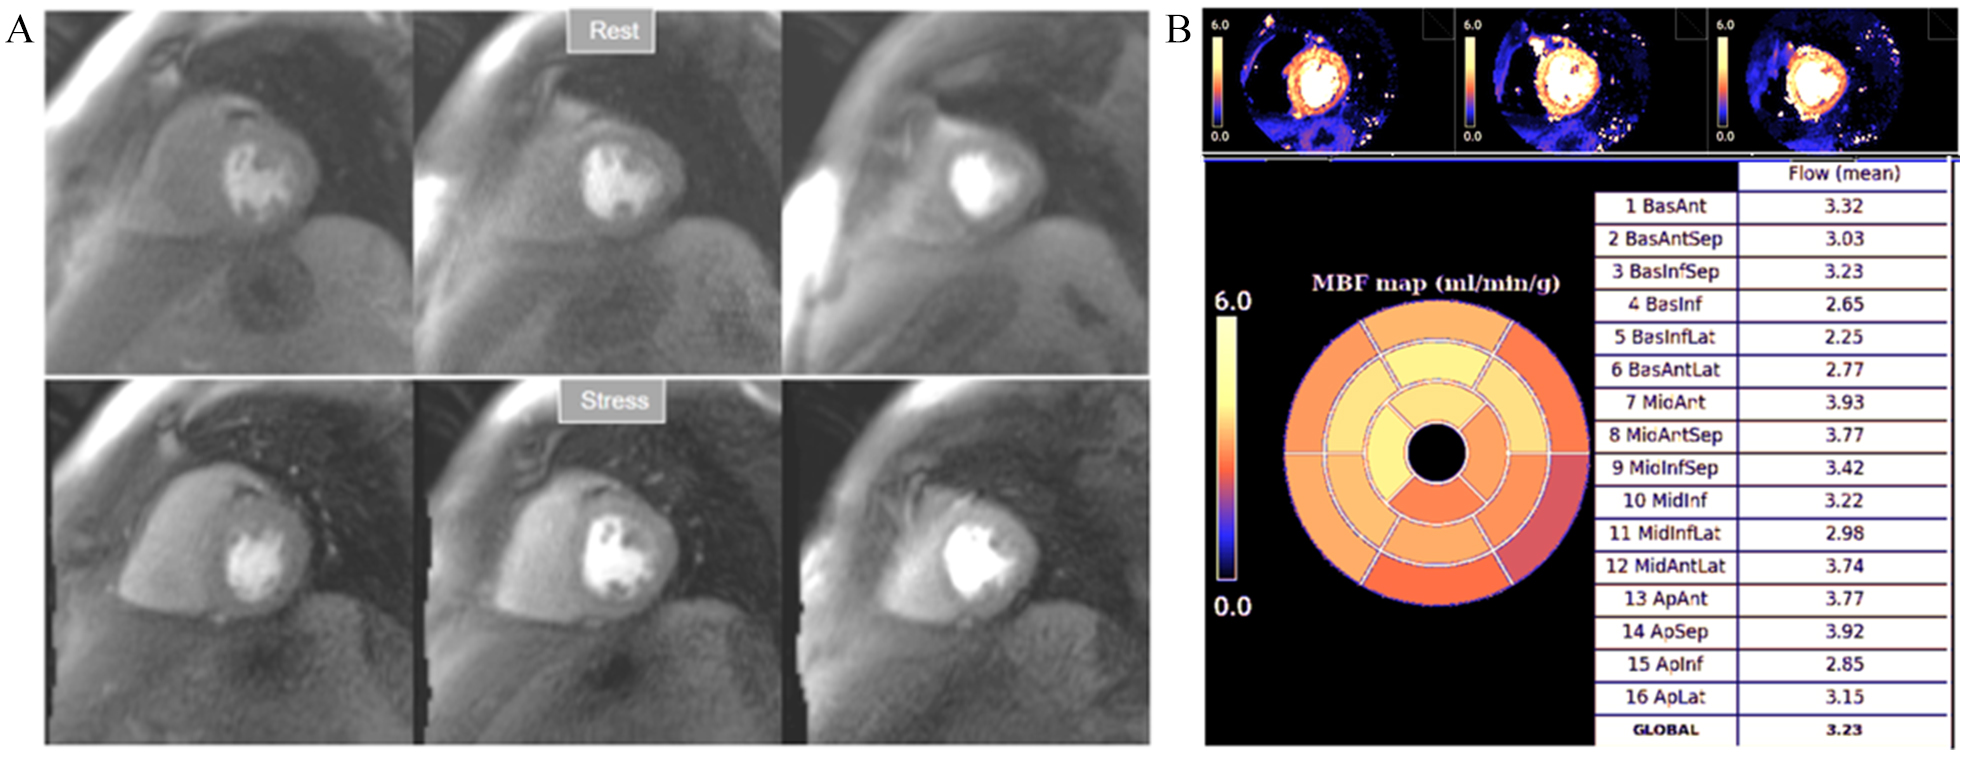

1.47 for the detection of significant obstructive lesions (

Fig. 33.Mildly abnormal perfusion mapping. (A) Rest and stress perfusion studies showing absence of induced visual defect. (B) Mildly reduced global stress MBF (left table), particularly in the subendocardial regions (right table), suggesting MVD.